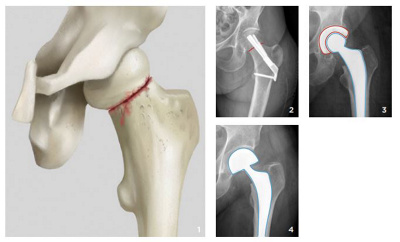

Am Beispiel der Schenkelhalsfraktur (vgl. Abb. 1) lassen sich die individuellen Überlegungen, die in ähnlicher Weise auch bei allen anderen Frakturen zur Anwendung kommen, exemplarisch aufzeigen:

Beim jungen und aktiven Patienten wird meistens versucht, das Hüftgelenk zu erhalten. Dazu wird so frühzeitig wie möglich in einer Notfalloperation der meist verschobene Bruch wieder präzise eingerichtet und mit Schrauben oder einem winkelstabilen Implantat der neusten Generation fixiert (vgl. Abb. 2). Um dem Bruch die notwendige Zeit zur Heilung zu geben, ist bei dieser Behandlungsart immer eine Entlastung an Stöcken für 6 bis 8 Wochen notwendig. Damit soll dem jüngeren Patienten ein Kunstgelenk, das oft eine beschränkte Lebensdauer hat und auch nicht bedenkenlos auf lange Zeit Extrembelastungen standhält, erspart werden.

Schenkelhalsfraktur

Abb. 1: Schenkelhalsfraktur

Abb. 2: In einer Notfalloperation wird der verschobene Bruch präzise eingerichtet und mit Schrauben oder einem winkelstabilen Implantat

der neusten Generation fixiert. Rot markiert ist die Frakturlinie.

Abb. 3: Totales Kunstgelenk der Hüfte mit künstlichem Schenkelhals, Hüftkopf und Hüftgelenkpfanne

Abb. 4: Künstlicher Schenkelhals und Hüftkopf ohne Hüftgelenkpfanne

Beim etwas älteren und aktiven Patienten wird meist ein totales Kunstgelenk der Hüfte implantiert (vgl. Abb. 3). Dabei wird sowohl der Hüftkopf als auch die Pfanne ersetzt, womit eine lange Funktionszeit, in der Regel von 20 Jahren und mehr, erreicht wird. Oft können die Komponenten, abhängig von der Knochenqualität, ohne Verwendung von Knochenzement eingesetzt werden. Mit zunehmendem Alter und damit verbundenen Nebenerkrankungen steigt auch das Risiko für Komplikationen und wiederholte Stürze. Gleichzeitig nehmen die Belastungsansprüche an das Gelenk im Alter ab. Um die Operationsdauer und den Blutverlust bei komplikationsgefährdeten Patienten so gering wie möglich zu halten, wird in diesen Fällen auf die Implantation einer Hüftgelenkpfanne verzichtet und nur der gebrochene Anteil des Oberschenkelknochens durch einen künstlichen Schenkelhals und Hüftkopf ersetzt (vgl. Abb. 4). Häufig wird zur Fixierung des Implantates zusätzlich Knochenzement verwendet, sodass bereits einen Tag nach der Operation wieder eine volle Belastung des operierten Beins möglich ist. Überlastungen von Hand- und Schultergelenken wegen einer länger andauernden Stockentlastung können so vermieden werden.